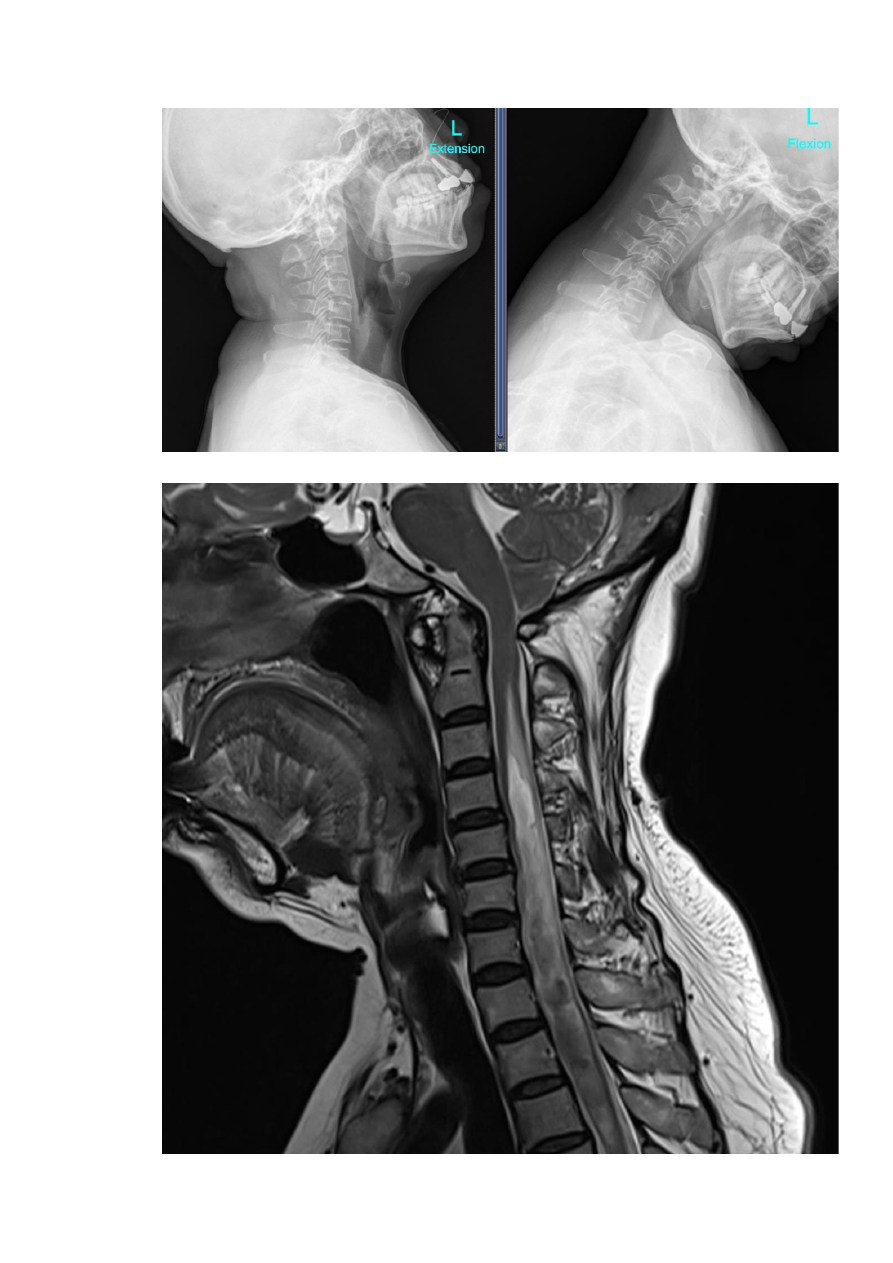

2)

MRI

:脊髓空洞(图

2

)。

影像学结果:

3

:术后

DR

显示复位良好

4

1

年、

提示脊髓空洞范围逐渐减小